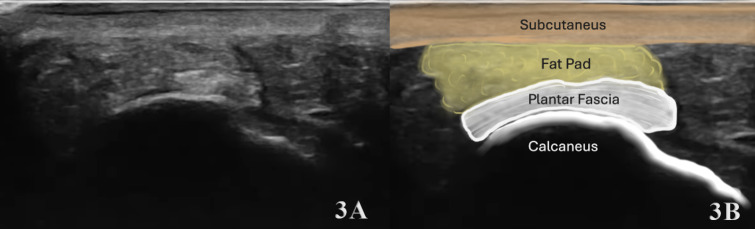

The plantar fascia is composed of fibrous connective tissue that forms a band running from the calcaneal tubercle distally to the toes. One of its main roles is to provide passive support to the medial longitudinal arch on the sole of the foot. This support is compared to a tie-rod tension producer during weight bearing. When loaded excessively during vocational or athletic activities, overuse in the form of plantar fasciitis can occur. Accurate diagnosis fascial injury is essential for appropriate treatment planning and optimizing patient outcomes. Diagnostic musculoskeletal (MSK) ultrasound offers a portable, real-time, and cost-effective alternative that is gaining traction in rehabilitation and sports medicine settings. MSK ultrasound has emerged as a valuable, non-invasive imaging modality for evaluating plantar fascia injuries including tissue hypertrophy or structural changes and damage at the calcaneal fascial enthesis. MSK ultrasound is adept at detecting changes in tendon tissue composition and integrity. Furthermore, this manuscript will review the utility of MSK ultrasound in evaluating the plantar fascial injury, including its anatomy, common injury patterns, sonographic techniques, and clinical implications for professional rehabilitation. By integrating MSK ultrasound into clinical practice, providers can improve the accuracy of diagnosis, enhance diagnostic confidence, monitor healing progression, and guide rehabilitation strategies to optimal patient outcomes.